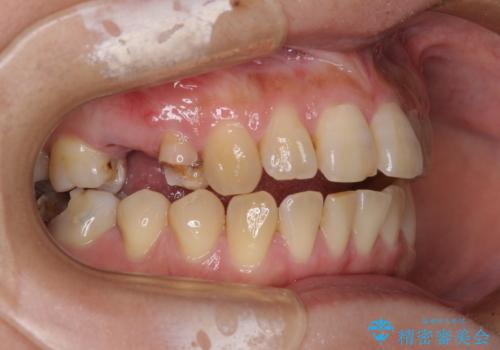

- 奥歯に問題が多くて困っているとのことで来院された患者様です。

開咬により奥歯のみが接触している状態で、前歯部にほとんど接触のない状態で、奥歯に非常に負担のかかる咬み合わせでした。

また、欠損や根管治療の必要な歯など、むし歯による問題も多く散見されました。

まずはむし歯の治療を行い、その後ワイヤー矯正にて咬み合わせを改善し、途中インプラント埋入を行い、矯正治療後に補綴治療を行うこととしました。